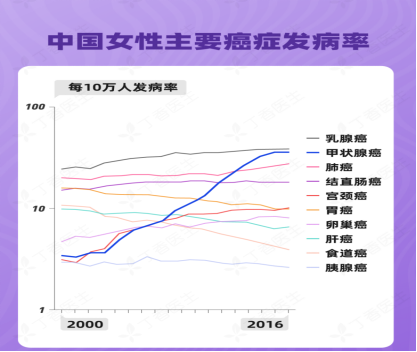

甲状腺癌是近年来全球范围内发病率增长最快的恶性肿瘤,在发病患者中女性较多。尤其是女性群体中的发病率更是居高不下,每年约有8500名女性发病,但死亡率低。